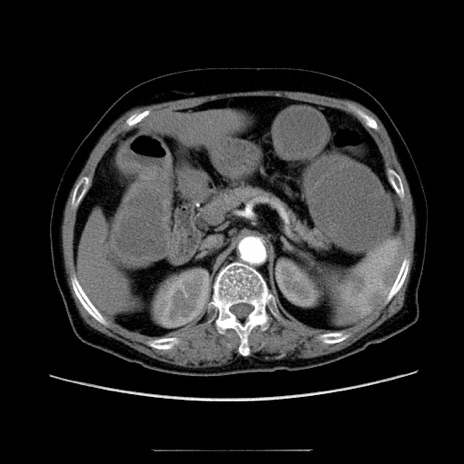

症例

冠状断像

【症例】70歳代女性

【主訴】お腹が張る

【現病歴】1週間くらい前から腹部膨満の自覚あり。昨日夜から増悪したため、本日救急外来受診。

【身体所見】意識清明、BT 36.5℃、BP 165/106mmHg、HR 80bpm、SpO2 98%、腹部:膨満、軟、自発痛・圧痛なし、触診にて不快感あり、腸蠕動音:減弱

【データ】WBC 12600、CRP 1.04